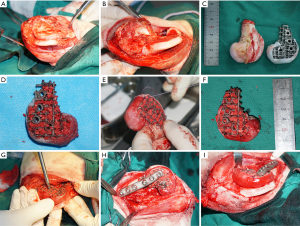

Fabrication of the Ti6Al4V frame and rounding off its distal surface

Computed tomography (CT) data of the goats’ right-hind knees were input into the Mimics software to construct frames matched to the lateral half of the distal femurs in the study goats. The basic regular hexagon unit had a side width of 1.9 mm and an inscribed circle diameter of 4.4 mm (Figure 3A,B,C). At the same time, the fixing plate and screw position on the frame was also designed. The designed frame and fixing system were fabricated with Ti6Al4V by EBM (Figure 3D,E,F). To round the frame’s distal surface, a poly (ε-caprolactone) (PCL) membrane with a thickness of 2 mm and a line spacing of approximately 100 µm was prepared by fused deposition modeling. Then, the prepared PCL membrane was softened in a 58 °C water bath and attached to the distal surface of the Ti6Al4V frame (Figure 3G,H,I).

A Ti6Al4V frame and internal fixation system with parameters of w=1.9 mm and d=4.4 mm that matched the defect of the 5.3 cm-long lateral half of the distal femur of the goat (Figure 3A,B,C) was prepared (Figure 3D,E,F). The distal end of the frame was covered with a 2 mm-thick PCL membrane having an average pore size of 132±15.6 µm (Figure 3G,H,I).

Repair of the bone defect in the lateral half of the goat’s distal femur